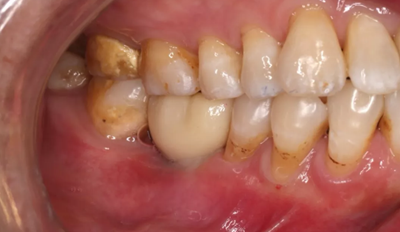

19、最終修復(fù)隨訪

修復(fù)完成6周隨診,牙齦形態(tài),色澤良好,咀嚼功能正常。

(攝于2018年7月27日)